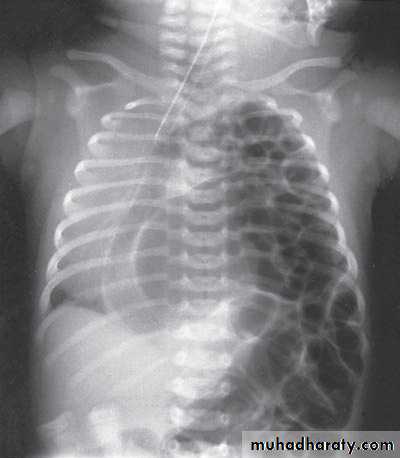

Respiratory Distress in the Newborn

Scaphoid abdomen